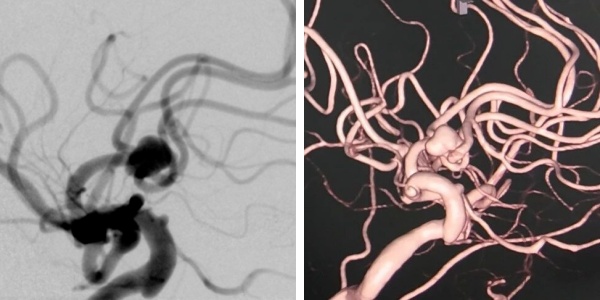

左为血管造影,右为三维成像

面对这两难困境,北京地坛医院神经外科经过全科讨论,决定启用既可以做血管内介入操作同时又可以实施开颅手术的平台——复合手术室。它可以很好地解决这一两难问题,通过术前全脑血管造影,三维成像可以清晰得显示动脉瘤的形态、大小、载瘤动脉、分支等。根据详细的影像,可以进一步决定手术的方案。

入院第二天上午,刘先生的手术开始了。先由介入团队进行全脑血管造影,三维成像证实了刘先生的前交通动脉瘤,直径最大约8毫米,瘤颈约5.2毫米,动脉瘤瘤颈累及5条主干血管!